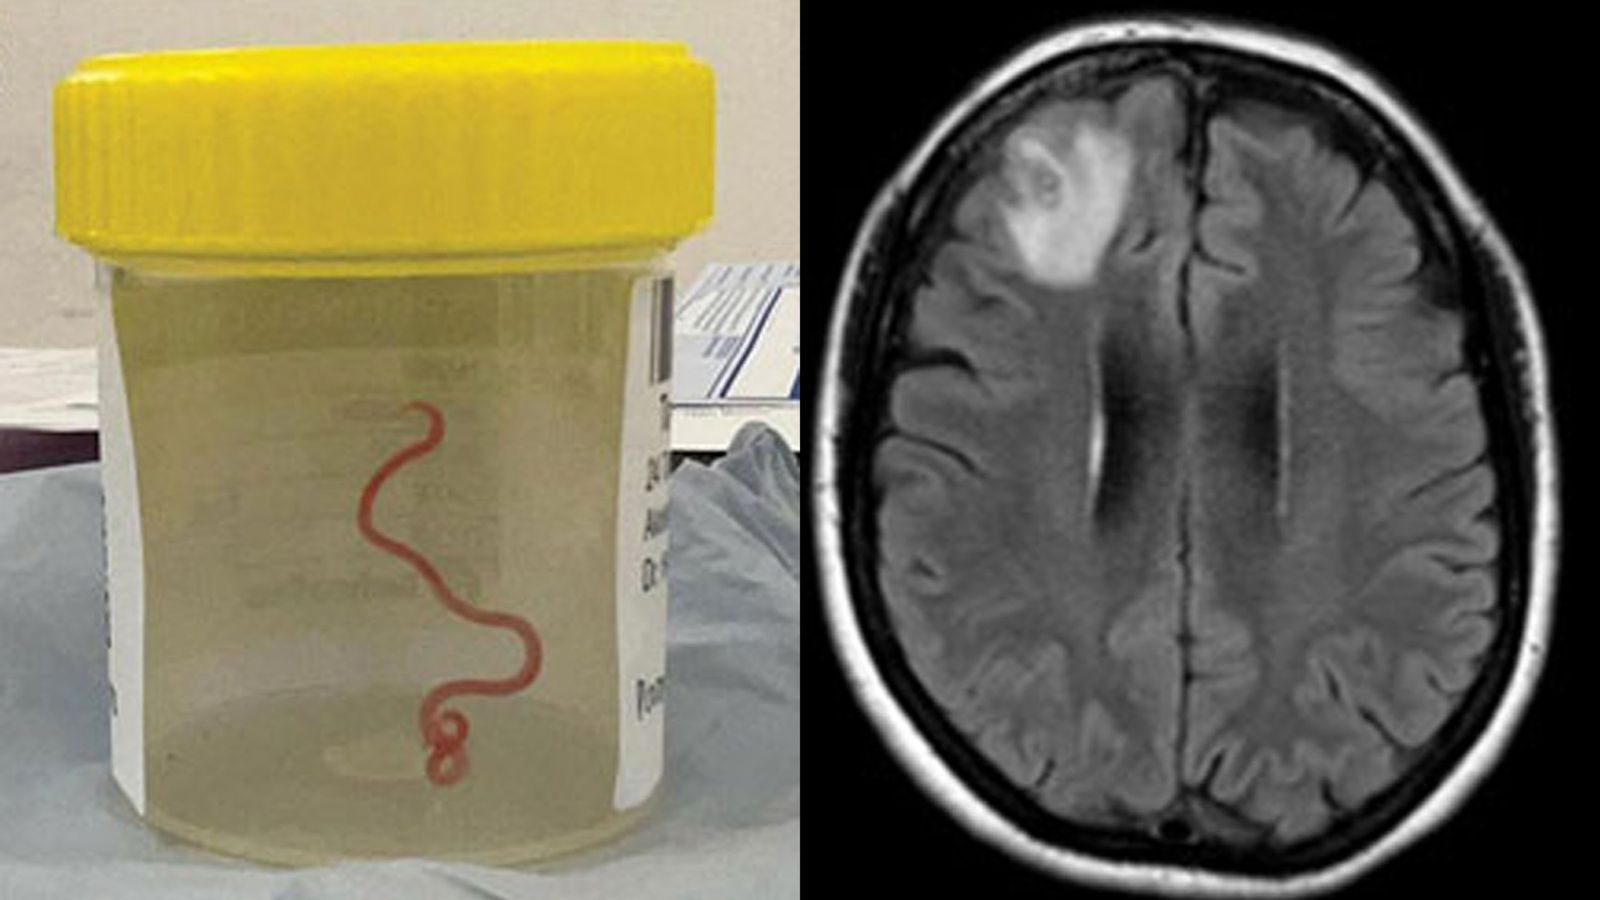

The live roundworm was removed from the patient’s right frontal lobe. Pics: Centers for Disease Control and Prevention

An MRI scan of her brain revealed that a motile helminth – a parasitic roundworm – was living in the right frontal lobe lesion of her brain.

Surgical intervention became the only option, and doctors successfully removed the roundworm, which measured 8cm (80mm) in length and 1mm in diameter.

The live roundworm after it has been removed from the patient’s right frontal lobe. Pics: Centers for Disease Control and Prevention

An image of the woman’s brain showing the right frontal lobe lesion